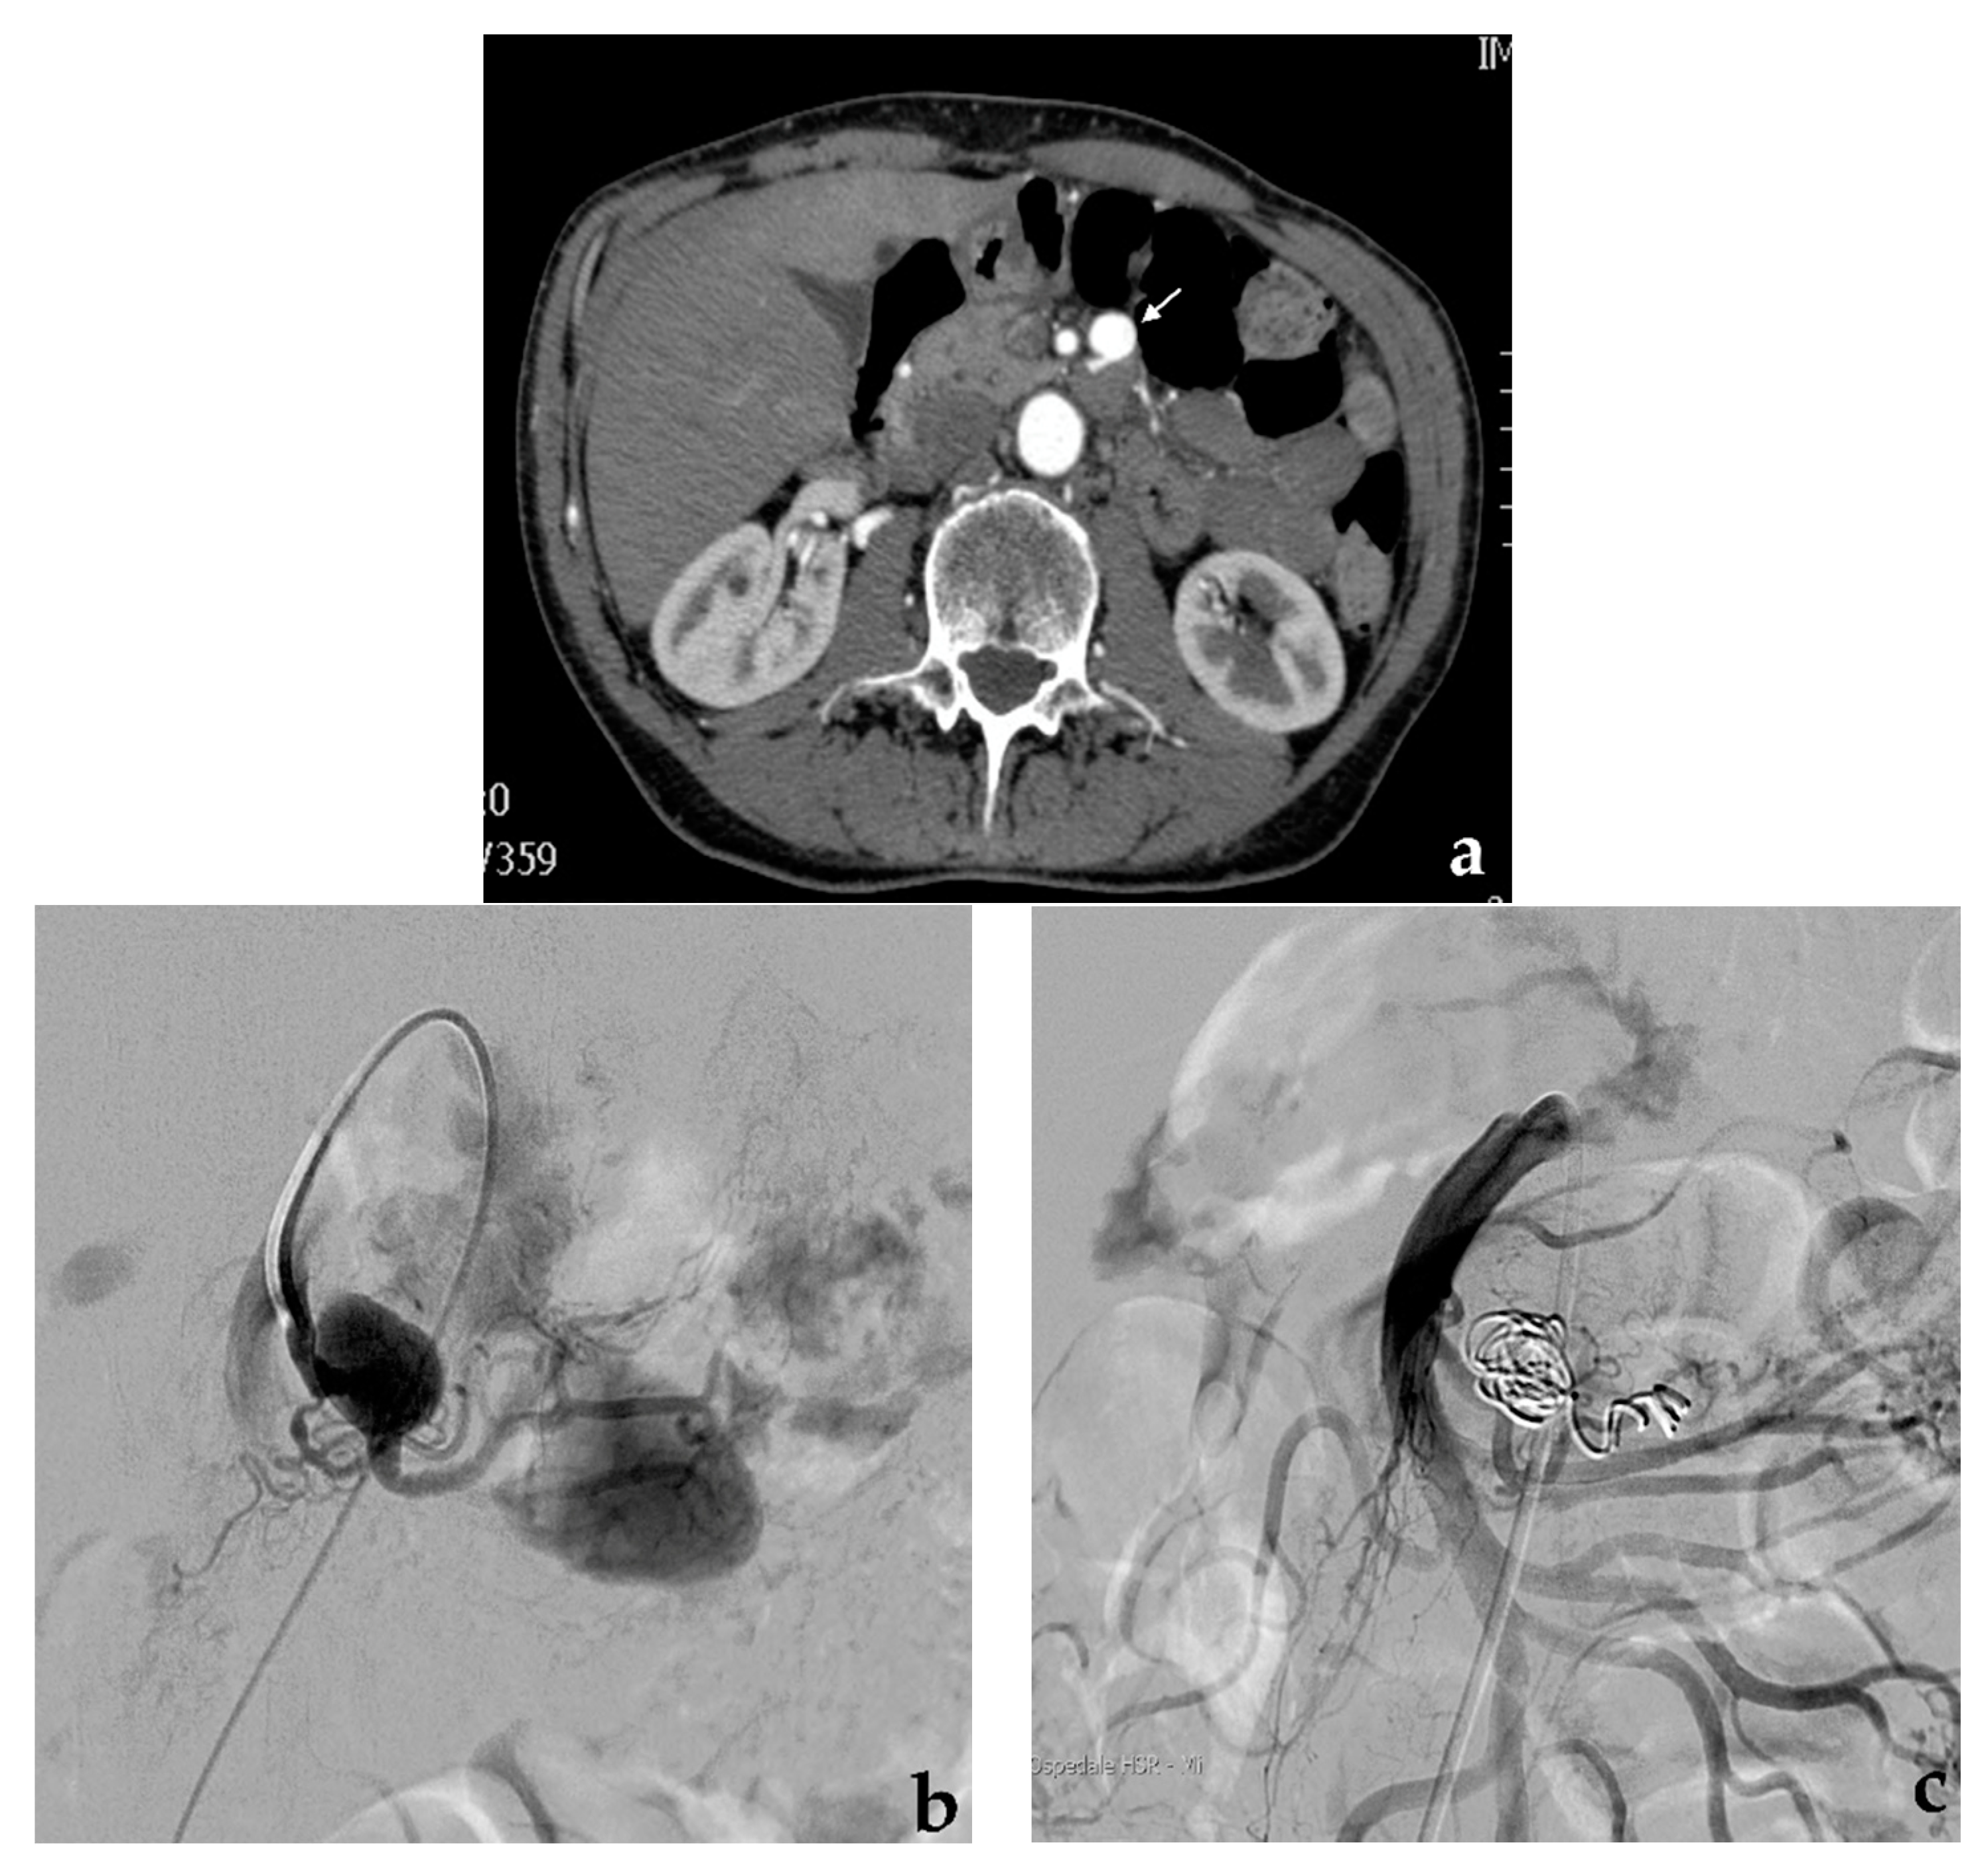

- Venturini, M.; Marra, P.; Colombo, M.; Alparone, M.; Agostini, G.; Bertoglio, L.; Sallemi, C.; Salvioni, M.; Gusmini, S.; Balzano, G.; et al. Endovascular treatment of visceral artery aneurysms and pseudoaneurysms in 100 Patients: Covered stenting vs transcatheter embolization. J. Endovasc. Ther. 2017, 24, 709–717. [Google Scholar] [CrossRef] [PubMed]

- Venturini, M.; Marra, P.; Colombo, M.; Panzeri, M.; Gusmini, S.; Sallemi, C.; Salvioni, M.; Lanza, C.; Agostini, G.; Balzano, G.; et al. Endovascular repair of 40 visceral artery aneurysms and pseudoaneurysms with the Viabahn Stent-Graft: Technical aspects, clinical outcome and mid-term patency. Cardiovasc. Interv. Radiol. 2018, 41, 385–397. [Google Scholar] [CrossRef]